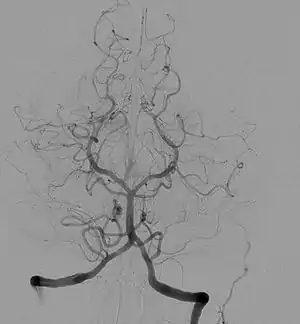

Angiogram of the brain showing a transverse projection of the vertebro basilar and posterior cerebral circulation. | |

Cerebral angiography

Cerebral angiography provides images of blood vessels in and around the brain to detect abnormalities, including arteriovenous malformations and aneurysms.[6] One common cerebral angiographic procedure is neuro-vascular digital subtraction angiography.[7][8]